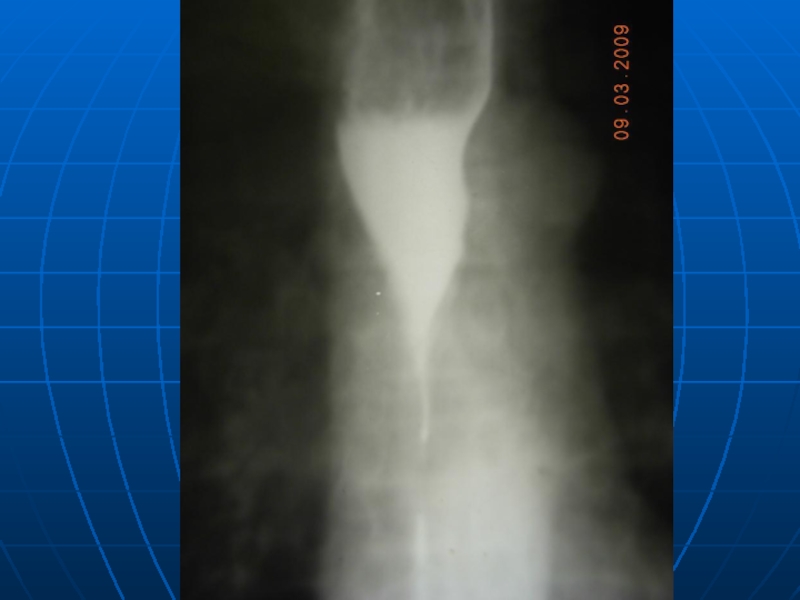

8. Кардиоспазм, ахалазия кардии